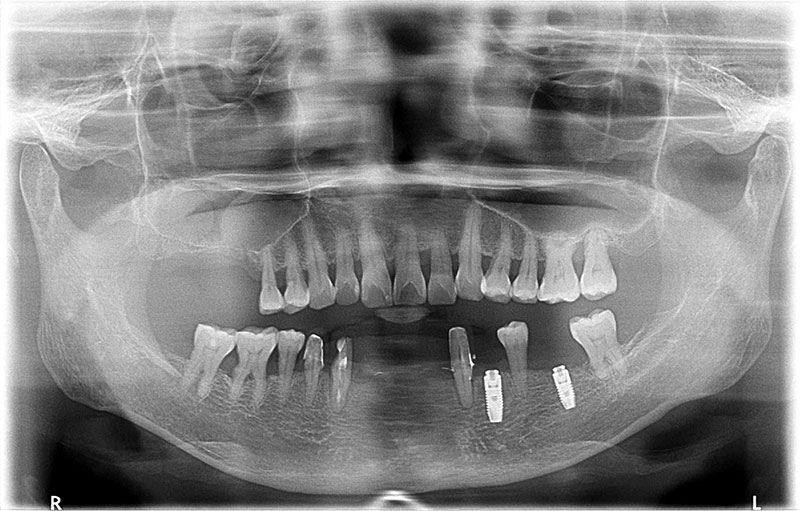

術前